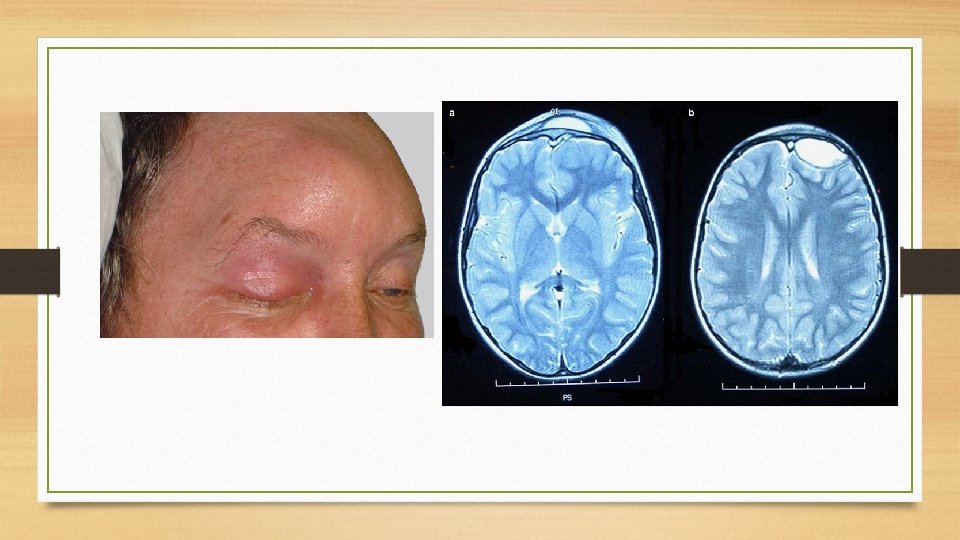

Chandler classification 1970 ♦Preseptal cellulitis ♦Orbital cellulitis without abscess formation ♦Orbital cellulitis with subperiosteal abscess ♦Orbital cellulitis with intra periosteal abscess ♦Cavernous sinus thrombosis

Subperiosteal abscess ♦Abscess formation deep to orbital periosteum ♦Proptosis ♦Impaired EOM with visual loss

Orbital abscess ♦Abscess formation within the orbit ♦Severe exophthalmos, chemosis, complete ophthalmoplegia ♦Visual impairment – optic neuropathy ♦Irreversible blindness

Orbital Complications Cavernous sinus thrombosis (Both intracranial and orbital complication) ♦Inflammatory process ophthalmic veins into cavernous sinus which thromboses and progress to abscess formation ♦Abrupt onset , Bilateral eye involvement. ♦Fever with chills & rigor ♦Rapidly progressive severe chemosis & proptosis ♦ 3, 4, 5, 6, nerve involvement , Loss of vision, dilated &fixed/sluggishly reacting pupil ♦Severe retinal engorgement. congestion & edema of optic disc ♦Meningitis-death

Intracranial complications Pathophysiology v v Close relation of paranasal sinuses to anterior and middle skull base Routes of spread -hematogenous or direct extension Retrograde septic thrombophlebitis Direct extension 1. Preformed routes like congenital or traumatic dehiscence 2. Sinus wall erosion 3. Existing neurovascular foramina like for optic and olfactory nerves, infraorbital foramen

Clinical features • History of recent URI with fever and symptoms of raised intracranial pressure. • Frontal or retroorbital head ache, nausea , vomiting, altered mental status • Nuchal rigidity, papilledema • Late finding- seizures, hemiparesis

MRI- Focal defects of enhancement with decreased cavernous carotid artery flow void MR angiogram MR venogram studies

Summary ♦ Orbit –most common structure involved CT with contrast of the sinuses and orbit > study of choice to evaluate orbital complications ♦ MRI with contrast – of brain and orbit is the study of choice for intracranial complications ♦ Common organism - strep pneumoniae, staph aureus, H – influenzae, moraxella, gram negative rods ♦ Intracranial complications are often poly microbial ♦ CVST- bilateral orbital pain, chemosis, proptosis and ophthalmoplegia ♦ Most common intracranial complications- meningitis- strep pneumoniae ♦ Intracranial abscess are associated with high mortality , neurological and developmental sequelae ♦ Osteomyelitis of frontal bone-----, potts puffy tumour ♦